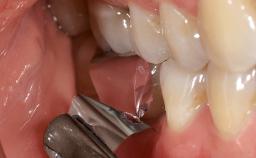

This case describes both a surgical and an anti-infective approach for the management of peri-implantitis, including treatment of the entire dentition to eliminate any deep periodontal pockets that could serve as reservoirs for bacterial re-colonization at the implant site. A 65-year-old female patient was referred to the periodontist in 2013 for assessment and management of an infection at implant 12. On examination, probing depths at implant 12 were 11 mm with suppuration and bleeding on probing.